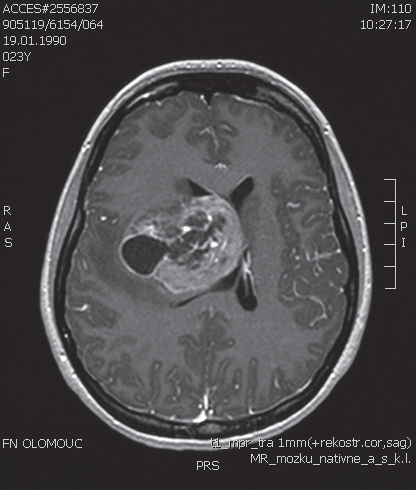

V naší kazuistice prezentujeme 25letou pacientku s negativní onkologickou rodinnou anamnézou, která dosud vážněji nestonala. Udávala asi 3 měsíce progredující bolesti hlavy a krční páteře, zvracení, postupně rozmazané vidění a parestezie horních končetin. Byla provedena magnetická rezonance, na které diagnostikován tumor mozku ve frontálním laloku vpravo, vyplňující frontální roh postranní komory velikosti 6x5 cm, midline shift, mass efekt. Dne 23. 9. 2013 ji byla na neurochirurgické klinice provedena neradikální exstirpace tumoru z parasagitální kraniotomie. Histologicky byl prokázán glioblastom multiforme gr. IV. Od 30. 10. 2013 do 12. 12. 2013 absolvovala konkomitantní radiochemoterapii (radioterapie do CLD 60,0 Gy) s temozolomidem (75 mg/m2 per os D1-42). Od ledna do dubna 2014 pokračovala v chemoterapii temozolomid solo v dávce 150 mg/m2, resp. od 2. cyklu 200 mg/m2 D1-5 ( Temodal tbl, celkem 4x). Na kontrolní MRI mozku ze dne 20. 5. 2014 byla prokázána progrese rezidua. Dne 4. 6. 2014 podstoupila druhou operaci, histologicky verifikován glioblastom multiforme s přechodem v gliosarkom. Snažili jsme se získat informace ze zahraniční literatury s léčbou gliosarkomu, bohužel se jedná o velmi vzácné onemocnění a údajů není mnoho. Nakonec byla zvolena léčba podle protokolu ICE (ifosfamid, carboplatina, etoposid), který je obdobou režimu PEI. Dávky: ifosfamid 1000 mg/m2 D1-3, carboplatina 110 mg/m2 D1 a etoposid 100 mg/m2 D1-3 v pětitýdenním cyklu. Pacientka zahájila 1. sérii od 1.7.2014 s podporou G-CSF (Neulasta s.c.). Léčbu tolerovala dobře, bez akutních či pozdních vedlejších nežádoucích účinků a významné hematologické toxicity. Po 3 cyklech podstoupila kontrolní MRI, kde popsána parciální regrese periferního sycení – rezidua tumoru. Po dalších 3 cyklech chemoterapie provedena restagingová MRI, kde popsána opět mírná regrese rezidua tumoru. Celkový stav pacientky se během léčby postupně zlepšoval, je mobilní, bez psychoorganického syndromu. Byly vysazeny kortikoidy, což vedlo k ústupu cushingoidního syndromu. Bylo rozhodnuto o pokračování v dalších 2 cyklech udržovací chemoterapie, na kontrolní MRI ze 14. 4. 2015 a 7. 7. 2015 popsána stabilizace onemocnění.